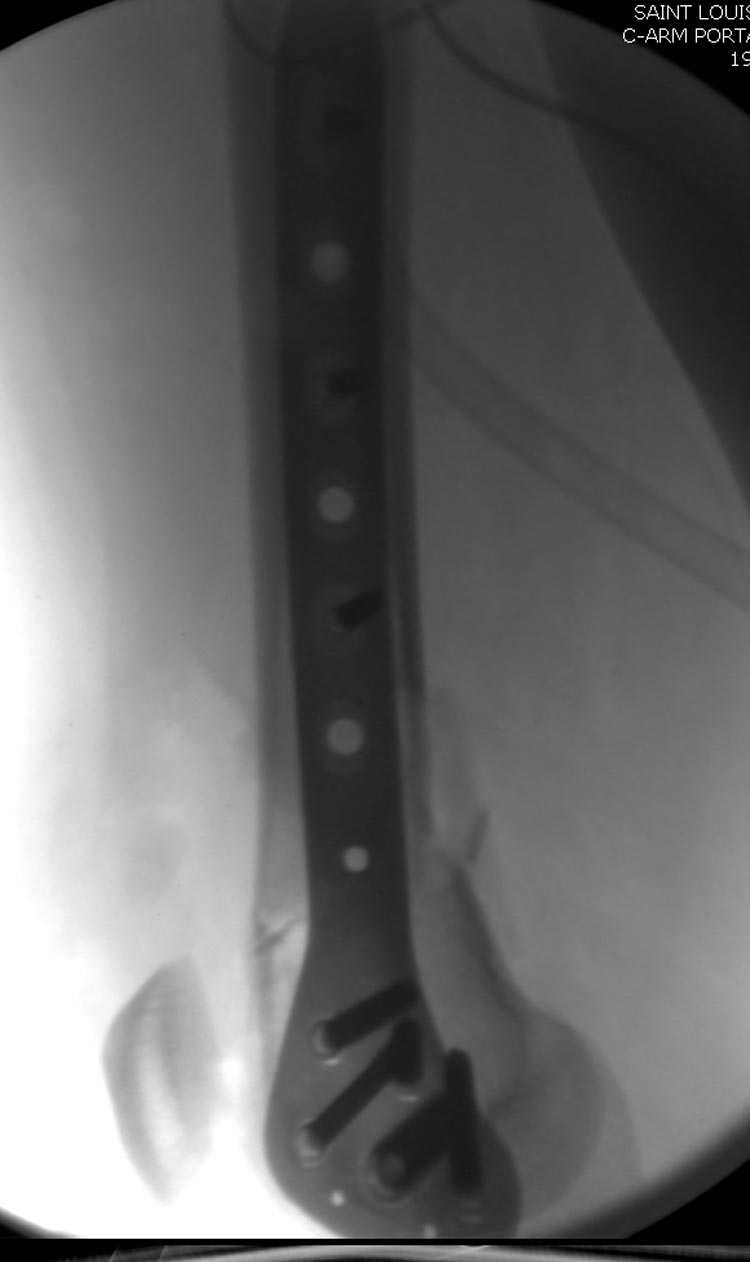

Почти все компании имеют пластины с угловой стабильностью, начиная от Stryker, Zimmer NCB и DePuy Polyaxial Plate . Если у NCB шуруп блокируется специальной шайбой, то Polyaxial Plate имеет вариабельный угол введения шурупов.

Поэтому такие меж и над- мыщелковые переломы более предпочтительным считается фиксировать мыщелковыми пластинами

Устанавливается из малого разреза "не вскрывая сустав" со стороны латерального мыщелка, и Insertion Jig позволяет установить пластину "мостовидно" перкутанно в проксимальном отделе, "не вскрывая и не трогая" место перелома.

Остановились на Liss пластине. Операция еще не состоялась.